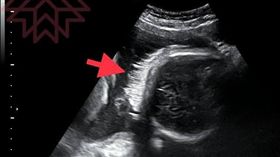

神奇!胎兒肚中長頭髮 超音波照曝光

超音波是既安全又便利的檢查,婦產科醫師可觀察胎兒在子...